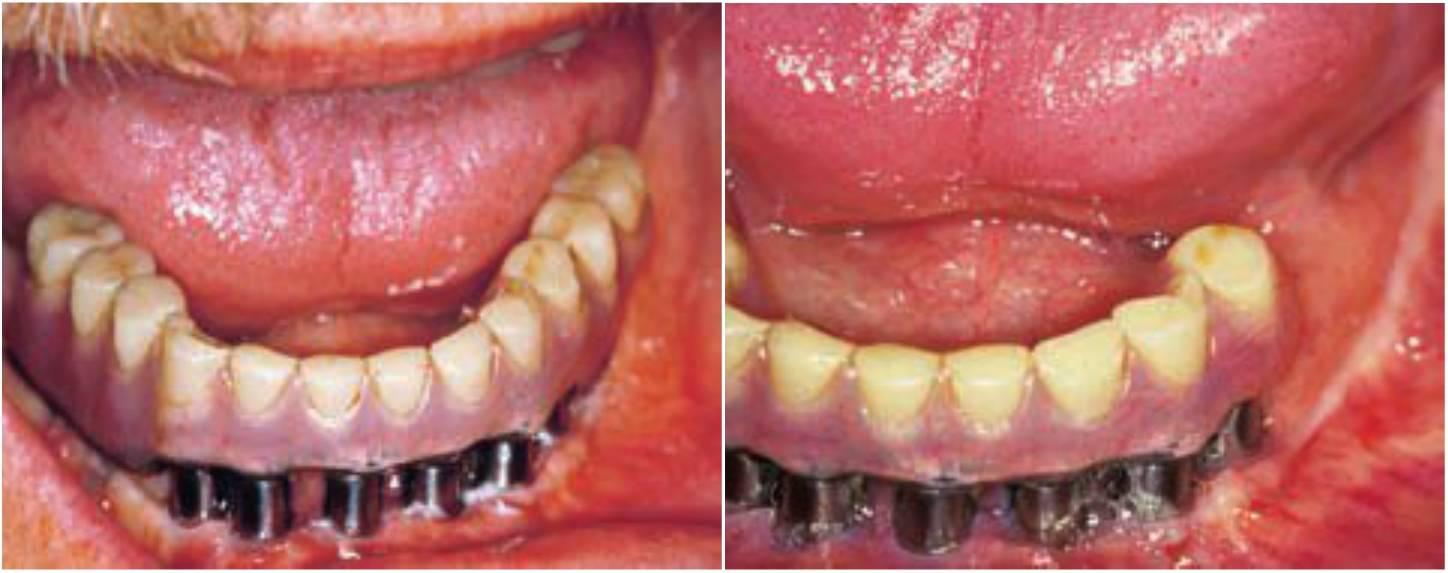

Al contrario que los dientes, los implantes no se extruyen cuando no existe un contacto oclusal. Por tanto, en los pacientes parcialmente edéntulos la férula nocturna se puede aliviar alrededor de las coronas sobre implantes, para que los dientes naturales remanentes soporten toda la carga. Por ejemplo, en una restauración implantológica maxilar se puede ahuecar el protector nocturno para que no se transmita ninguna fuerza oclusal sobre la corona del implante. Cuando la reconstrucción está en la mandíbula, se alivian las superficies de la férula nocturna del maxilar en oclusión con las coronas sobre implantes, para que no se transmita ninguna fuerza oclusal sobre los implantes (fig. 6-8).

También se debe aliviar la oclusión de los voladizos posteriores mandibulares de las rehabilitaciones de arcadas completas con implantes, con las férulas nocturnas. Cuando un cuadrante posterior de implantes soporta una prótesis fija en el maxilar superior, teniendo como antagonistas los dientes naturales inferiores, se debe colocar un material de refuerzo blando alrededor de las coronas sobre implantes que actúe como un elemento de alivio del estrés y que disminuya el impacto de la fuerza sobre la restauración (fig. 6-9).

Cuando las dos arcadas son rehabilitacion es completas sobre implantes, la férula nocturna proporciona únicamente contactos anteriores durante la oclusión céntrica y las excursiones mandibulares. Por tanto, se reduce la fuerza parafuncional en los dientes/implantes anteriores y se elimina en las regiones posteriores.